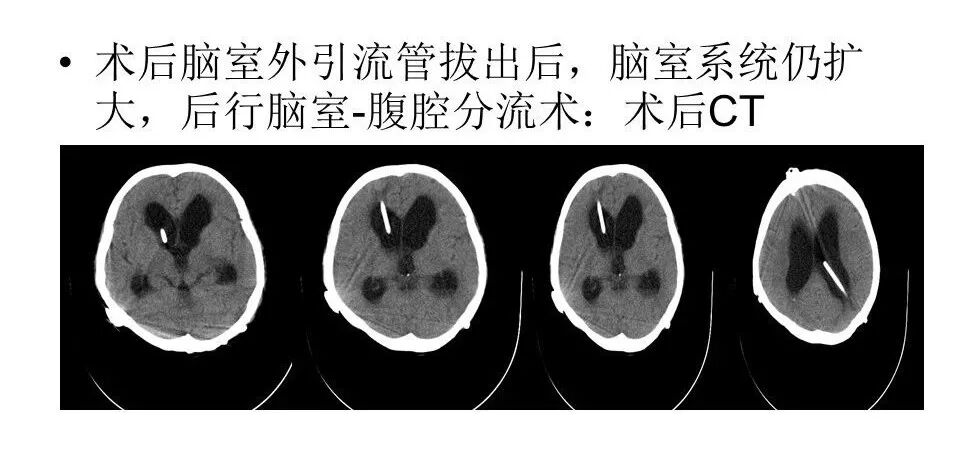

远外侧入路全斜坡巨大脑膜瘤显微手术1例